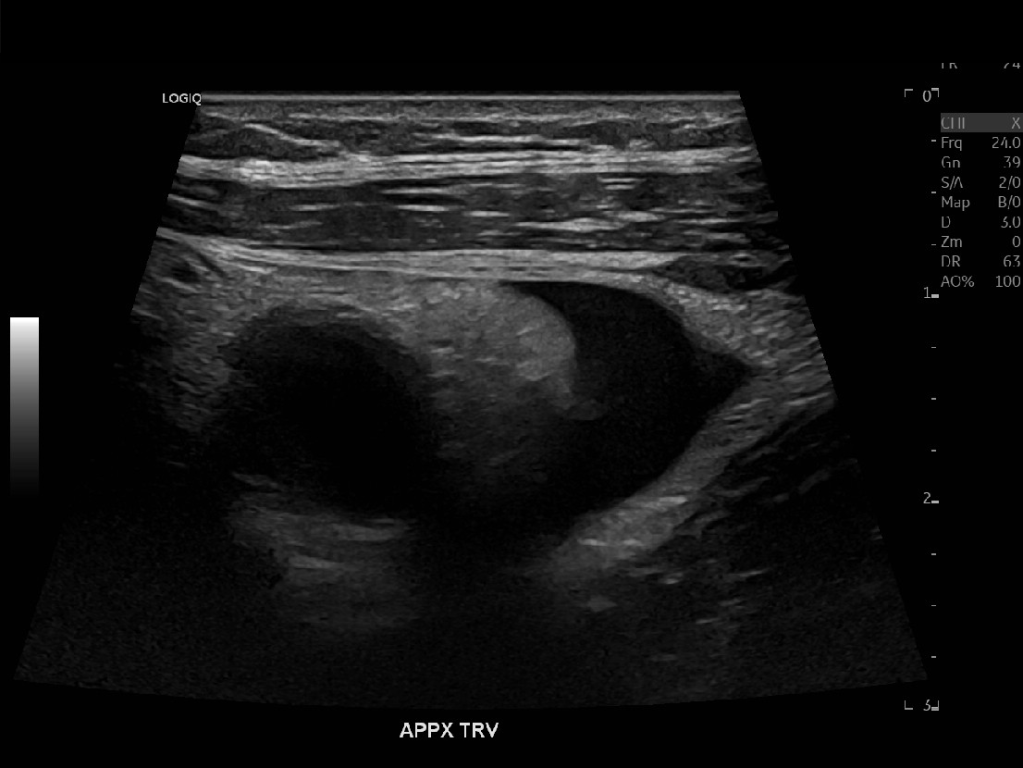

Appendicitis 13

Acute appendicitis @ 1 cm with L2-9mhz and L6-24mhz transducer GE Logiq e10.